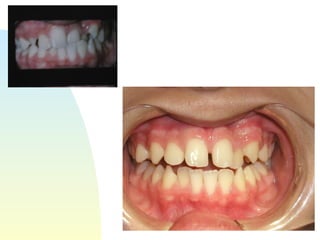

Patient   : J.R, male DOB :7/20/91, start of tx age: 12yr 9mo Ethnicity : American-born Hispanic, English-speaking Health Hx :  WNL, unremarkable Dental Hx :TMJ=WNL, OH=B+, midline=on, molar R&L= Cl 1, OB=40%, OJ= 1mm, dental anterior cross-bite, crowded max & mand anteriors, caries #15-O, #18-O,B, perio=WNL Psychosocial : Parents are separated,  1 younger sister,1 older sister.  Mom had ortho tx --- 4 premolars & 4-3rd molars extracted, “My braces hurt and I don’t want a lot of teeth pulled on my son”. Chief complaint :  “I don’t like the way my teeth stick out in front.”